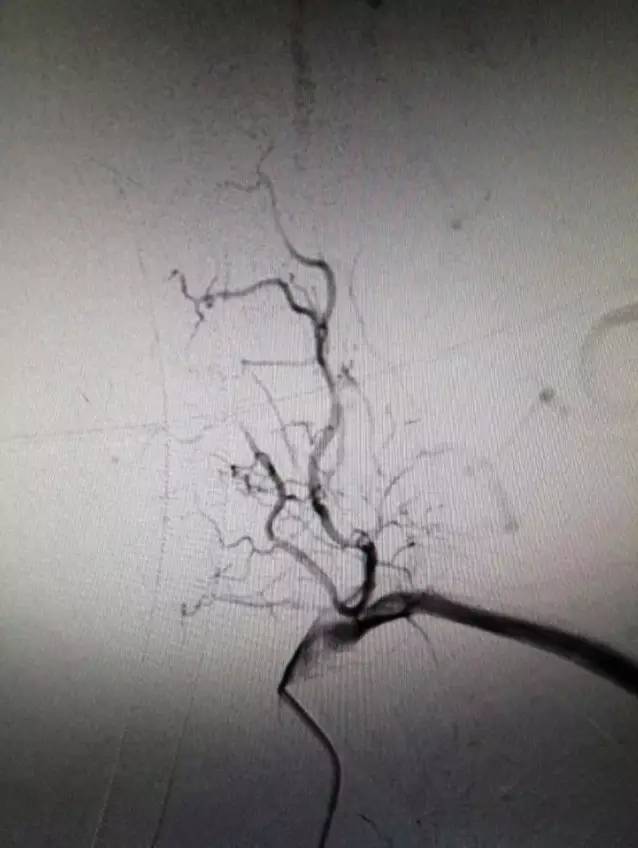

▼左锁骨下动脉造影显示左椎动脉闭塞,椎动脉V3段通过肌支代偿见返流。